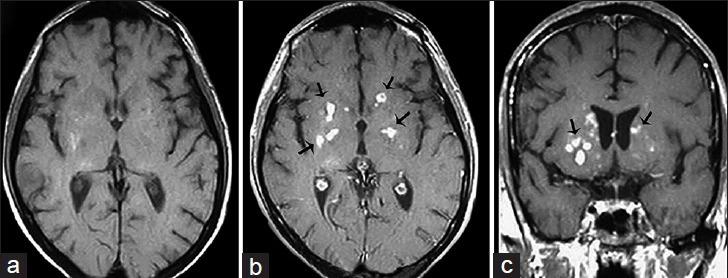

中枢神经系统真菌感染:图文综述

Fungal Infections of the Central Nervous System: A Pictorial Review.

Fungal infections of the central nervous system (CNS) pose a threat to especially immunocompromised patients and their development is primarily determined by the immune status of the host. With an increasing number of organ transplants, chemotherapy, and human immunodeficiency virus infections, the number of immunocompromised patients as susceptible hosts is growing and fungal infections of the CNS are more frequently encountered. They may result in meningitis, cerebritis, abscess formation, cryptococcoma, and meningeal vasculitis with rapid disease progression and often overlapping symptoms. Although radiological characteristics are often nonspecific, unique imaging patterns can be identified through computer tomography as a first imaging modality and further refined by magnetic resonance imaging. A rapid diagnosis and the institution of the appropriate therapy are crucial in helping prevent an often fatal outcome.

中枢神经系统(CNS)真菌感染对免疫功能低下的患者构成威胁,其发病主要取决于宿主的免疫状态。随着器官移植、化疗及人类免疫缺陷病毒感染病例的增多,作为易感宿主的免疫功能低下患者数量不断增加,中枢神经系统真菌感染也更为常见。它们可能导致脑膜炎、脑炎、脓肿形成、隐球菌瘤及脑膜血管炎,疾病进展迅速且症状常相互重叠。尽管影像学特征通常不具有特异性,但计算机断层扫描作为首选成像方式可识别出独特的影像模式,磁共振成像则可进一步完善。快速诊断并采取恰当治疗对于预防往往致命的后果至关重要。